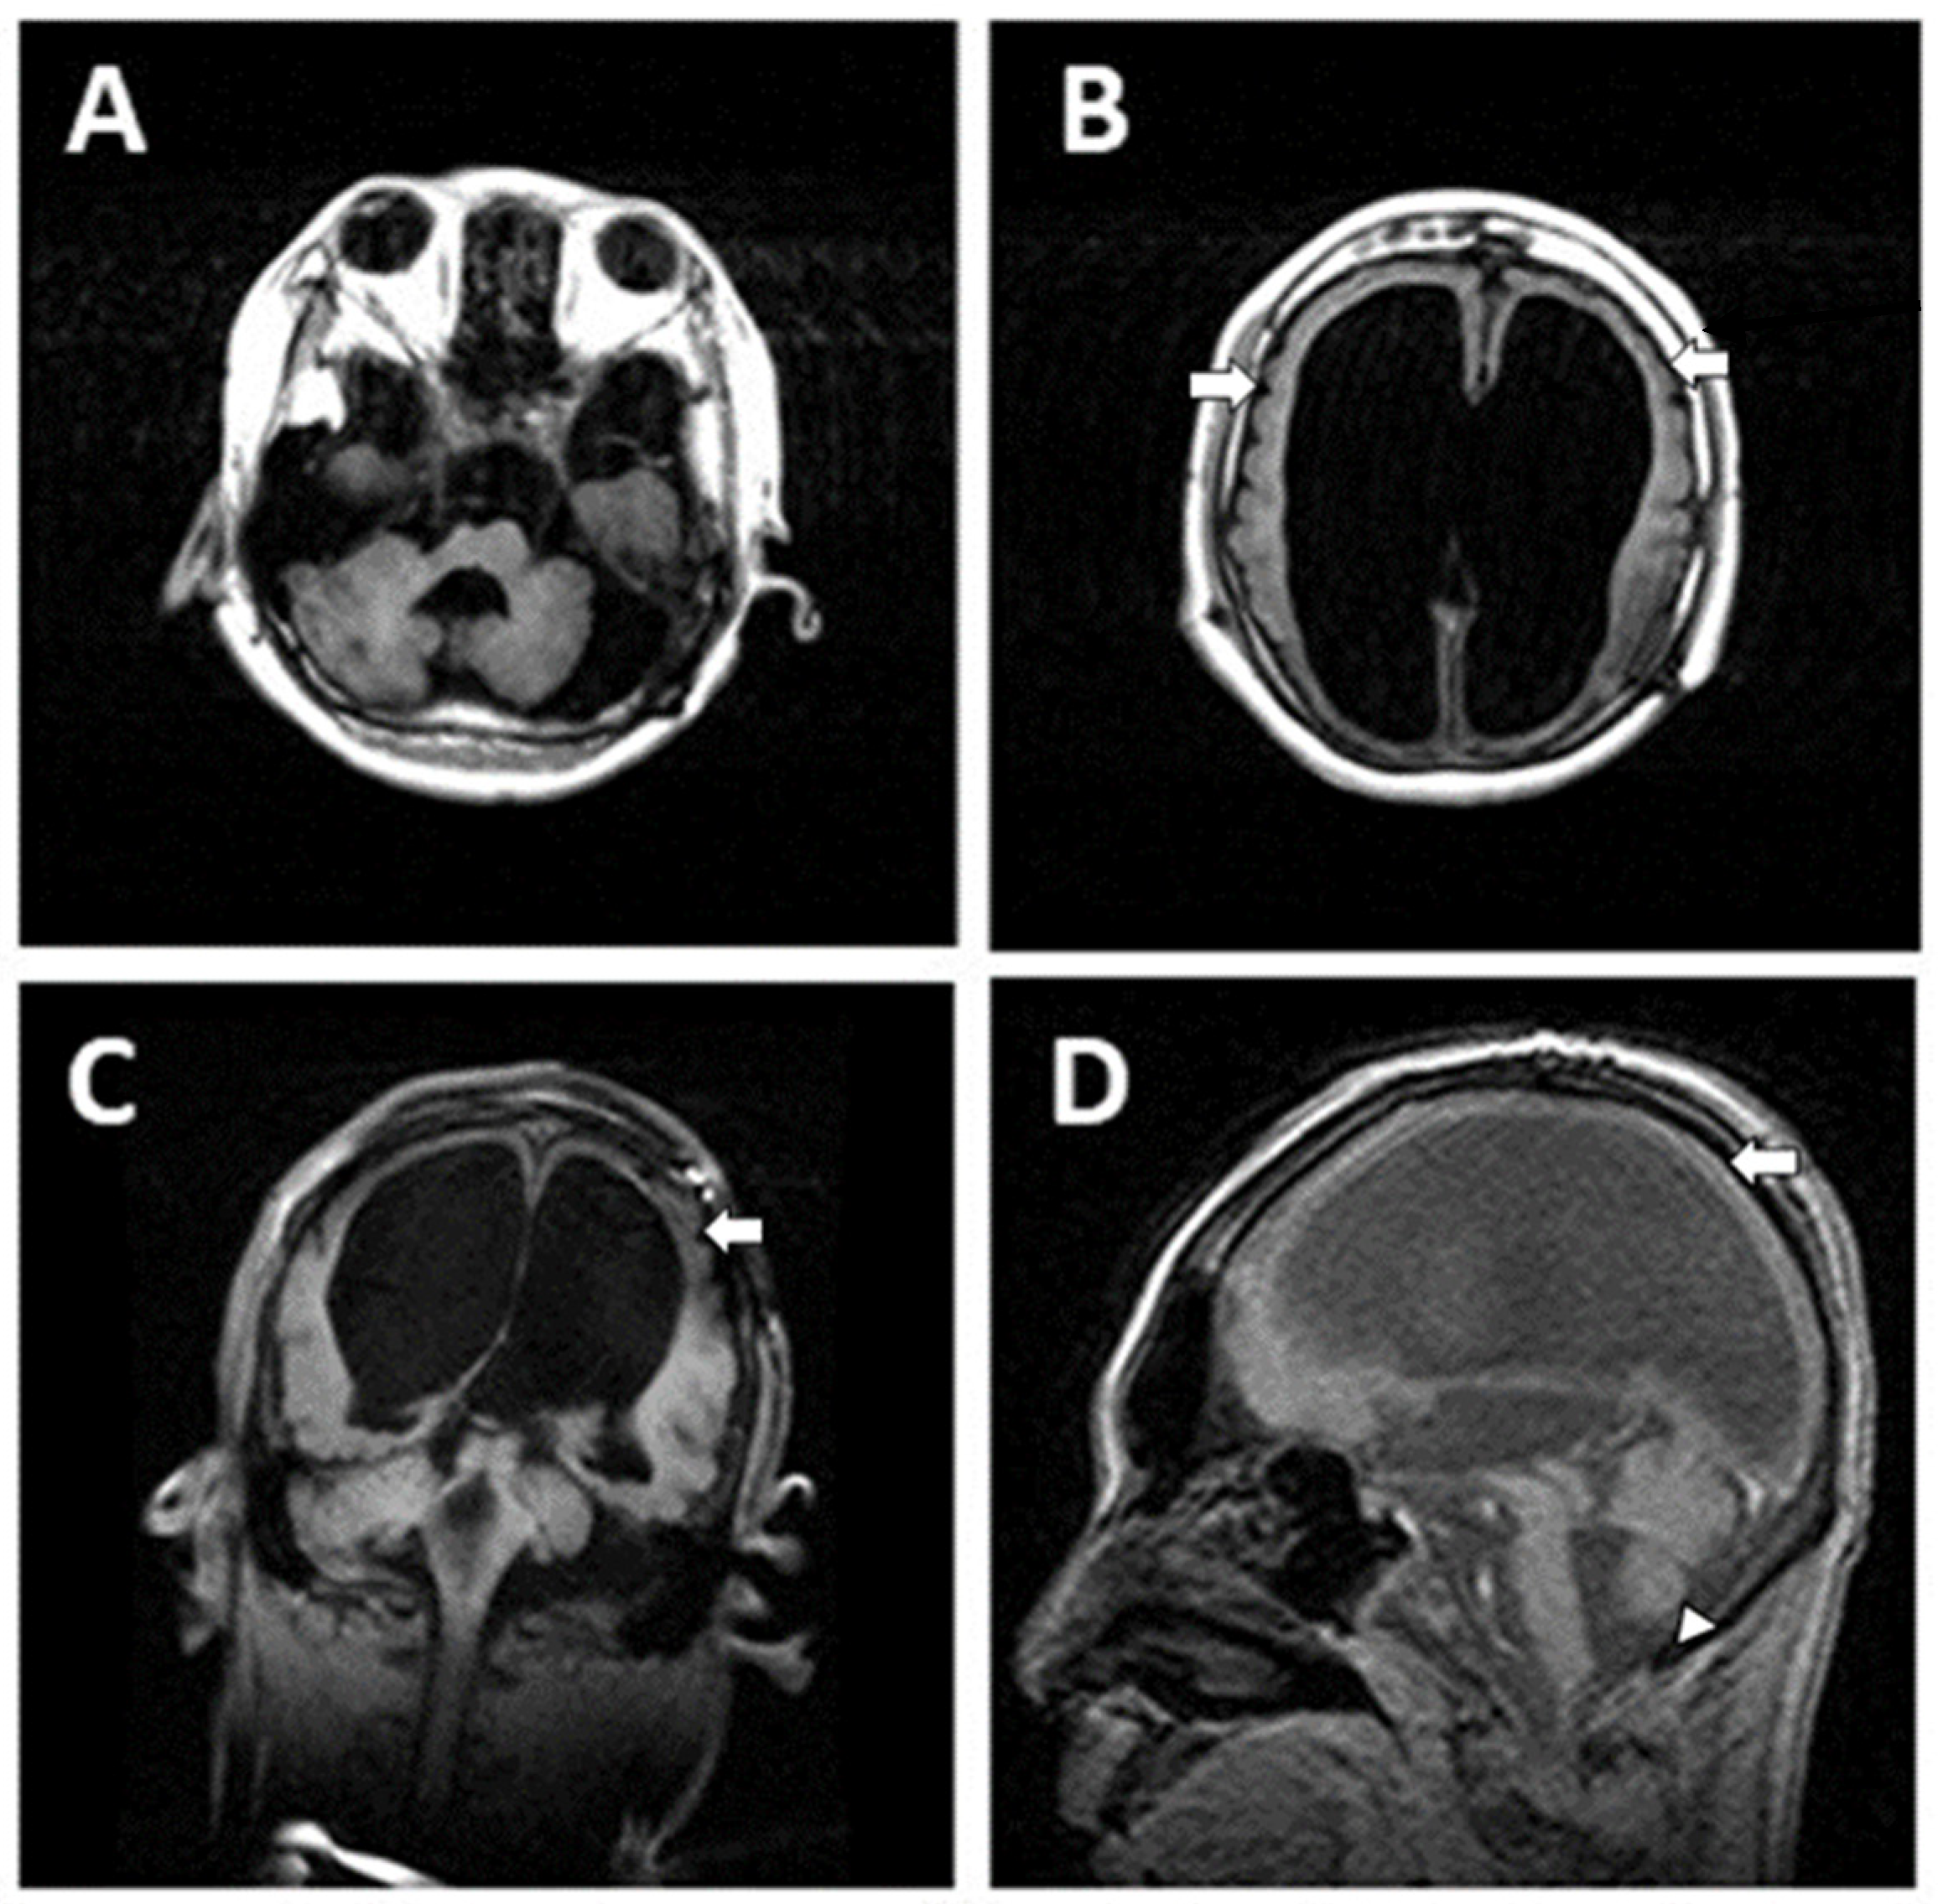

2.1. Case 1

Patient Information